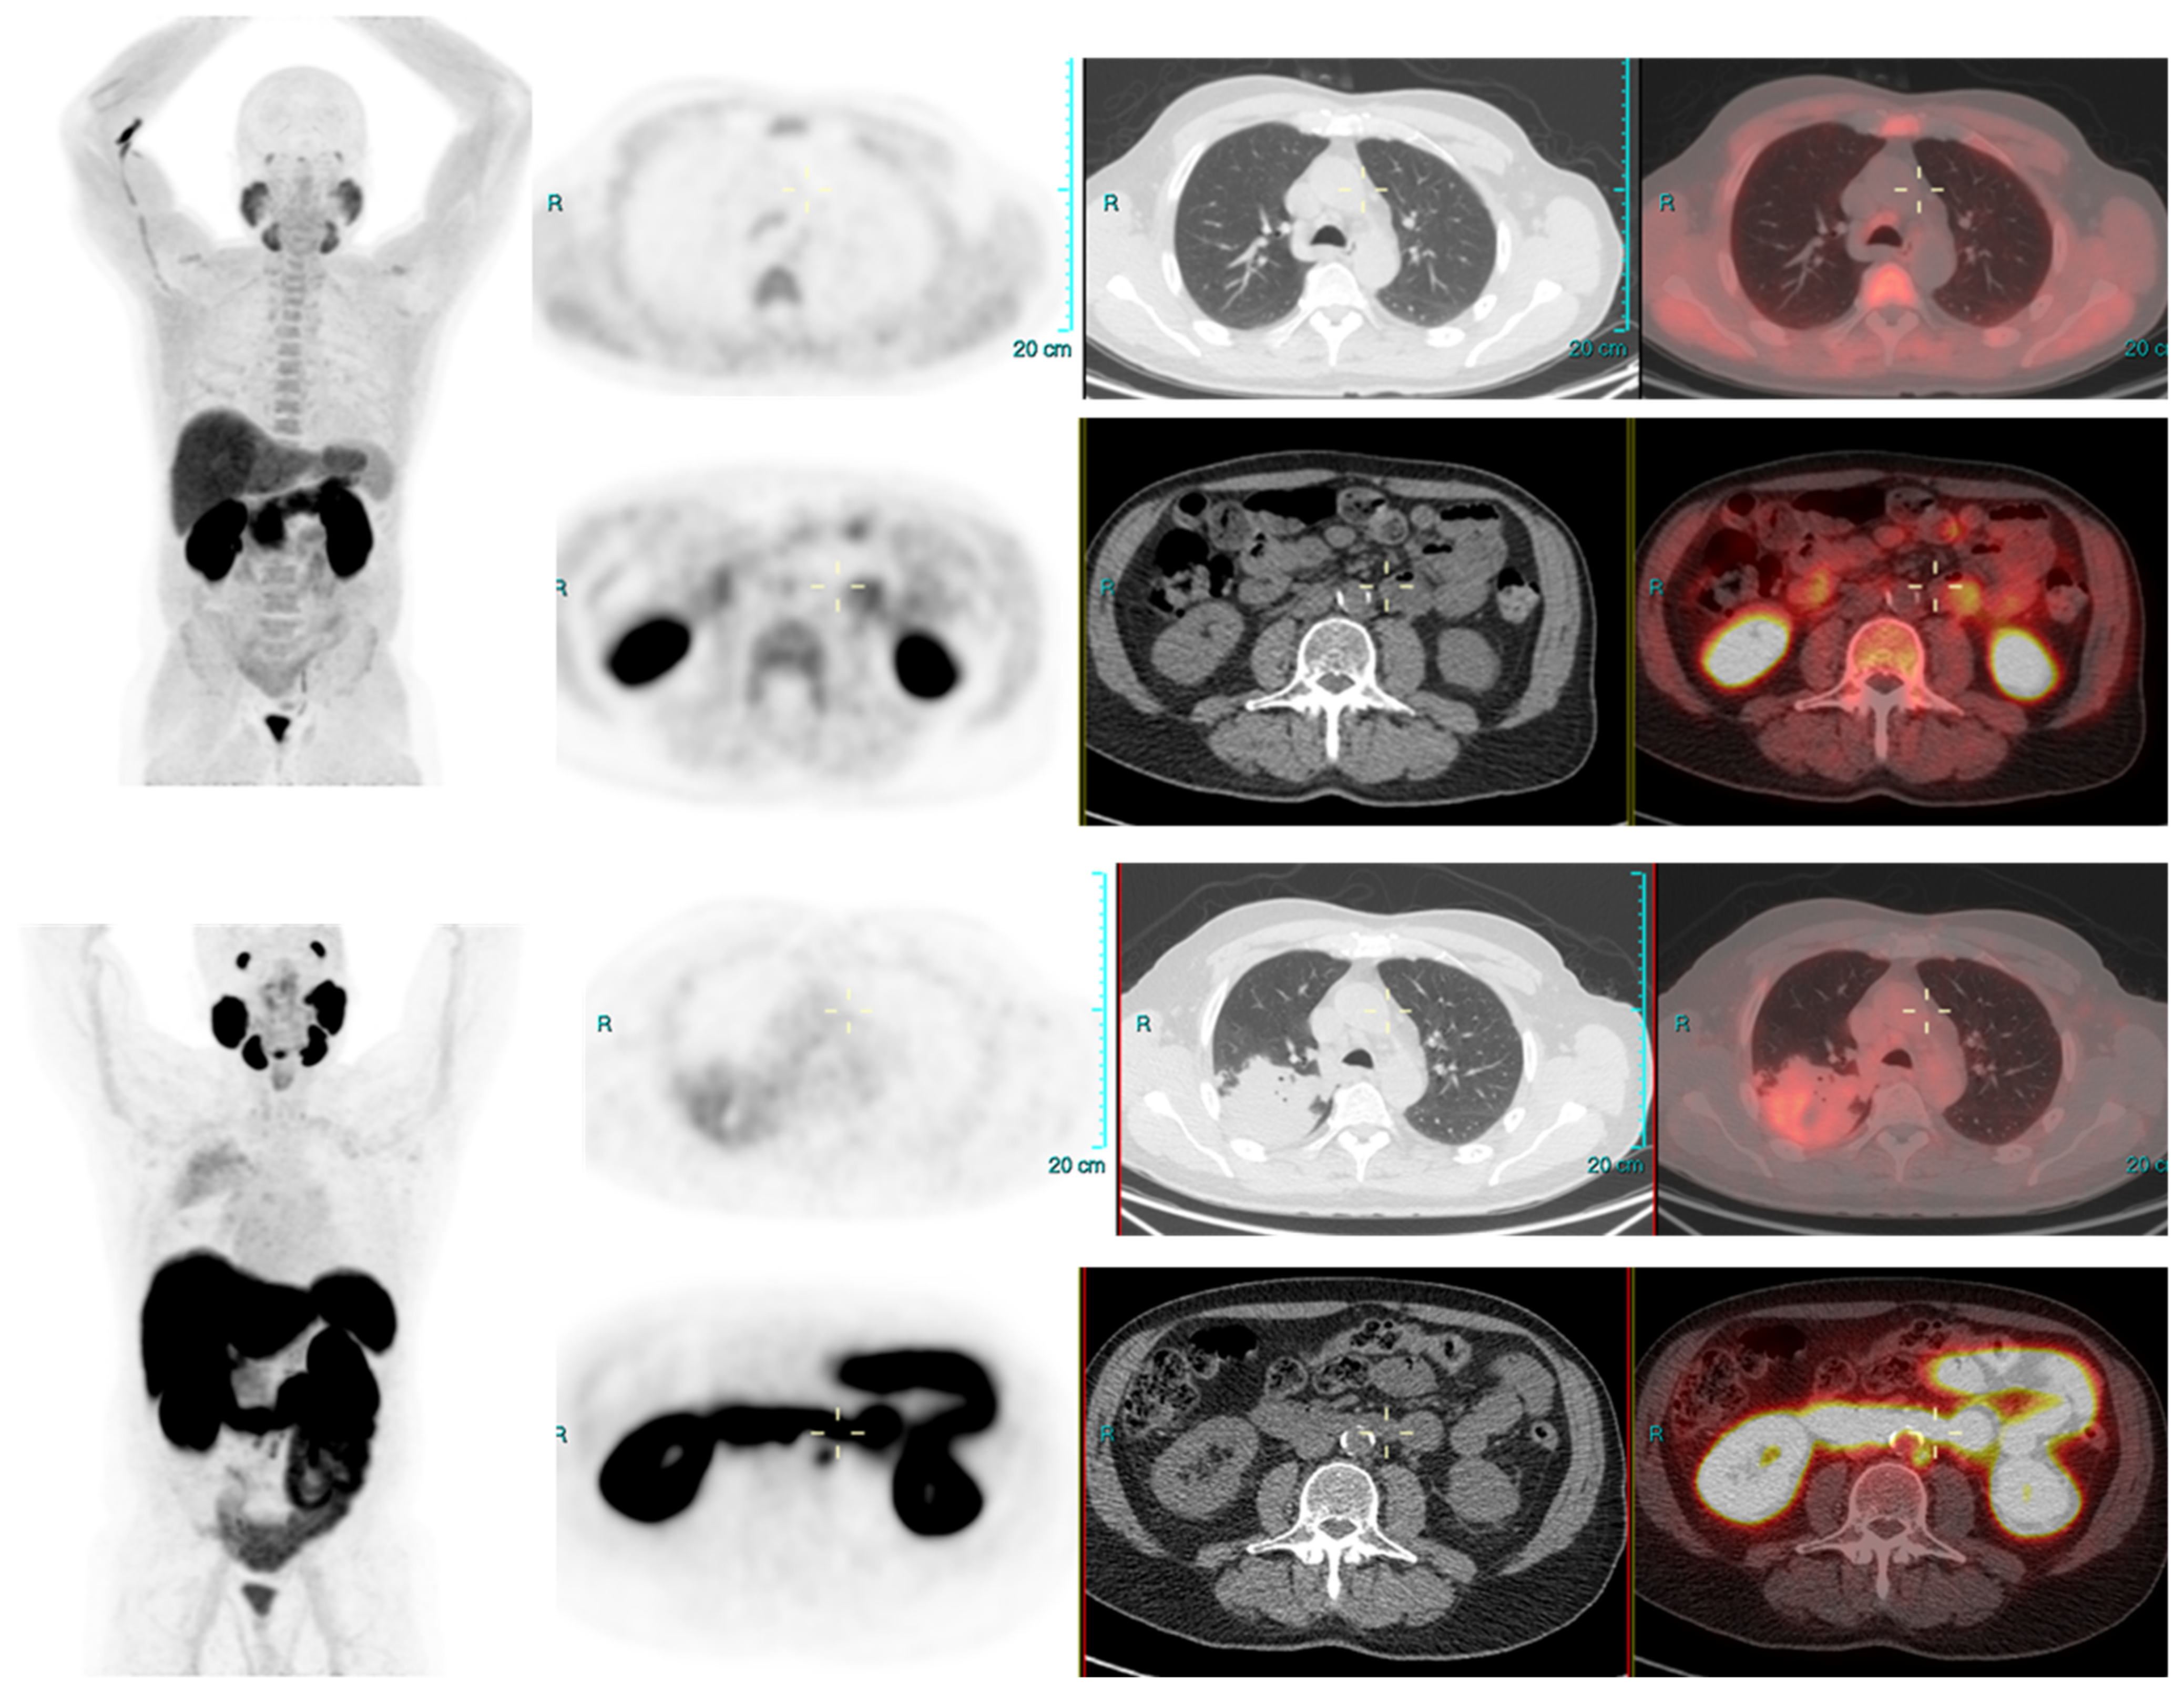

We conducted a separate subgroup analysis of 61 patients (Table 4) who had repeat imaging. Thirty had indeterminate findings on initial PSMA PET CT and the findings changed to a positive lesion in 14 (10 with known small indeterminate pelvic lymph node and four with known indeterminate prostate focus, PSA increase of 0.7 to 3.0 in 6 months), negative in eight (four with pelvic lymph node, four with uptake in bones on prior PET CT, PSA increase of 0.13–2). Six patient had the same indeterminate small pelvic lymph node, two had the same indeterminate retroperitoneal lymph node (PSA increase of 0.4 to 2.5). Overall, the follow-up PSMA PET CT was able to conclude in 24/30 patients on follow-up. Of the 31 patients who had repeat PSMA PET CT scans done for a further rise in PSA levels (PSA rise range 0.3–10), 24 had new lesions (prostate lesion in four, prostate and seminal vesicle involvement in four, pelvic/retroperitoneal lymph nodes in 12, new bone lesion in four) and eight had negative scans even on repeat imaging (PSA rise 0.3–2.3). For example, patient in Figure 2 had negative scan at PSA of 3.4 ng/mL, PSA velocity of 1.3 ng/mL in six months. The uptake in right humerus is at the site of known prior humerus fracture and therefore it was categorized as PSMA RADS 1 B (7). Another patient in Figure 3 had and indeterminate lymph node at PSA 6.5 ng/mL, after rise of 3 ng/mL in 2 years, it was categorized as RADS 3A(7). An interesting finding in this case was the consolidation changes in the right upper lobe, which resolved in a follow-up CT performed after 2 months (Figure 4).

Figure 2.

Radical prostatectomy—Negative scan at PSA 2.1 and 3.4 ng/mL, PSA rise of 1.3 ng/mL after 6 months. PSMA RADS 1 B, due to uptake in prior known humeral fracture.